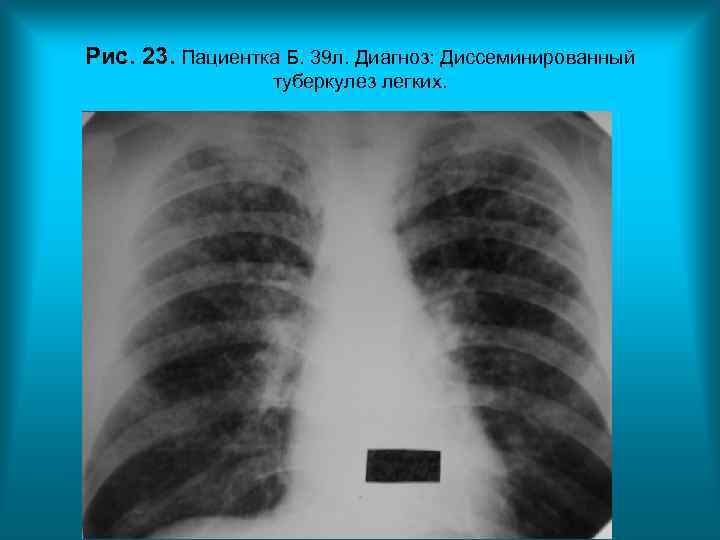

Рис. 23. Пациентка Б. 39 л. Диагноз: Диссеминированный туберкулез легких. Н. С. Воротынцева. С. С. Гольев Рентгенопульмонология